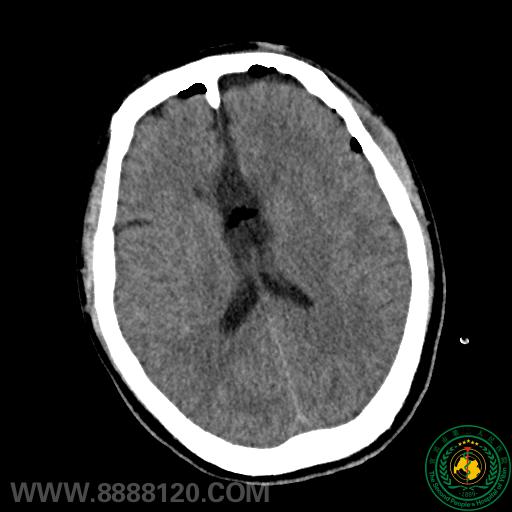

图示患者术前头颅CT情况:未见颅内实质性占位肿瘤病变。